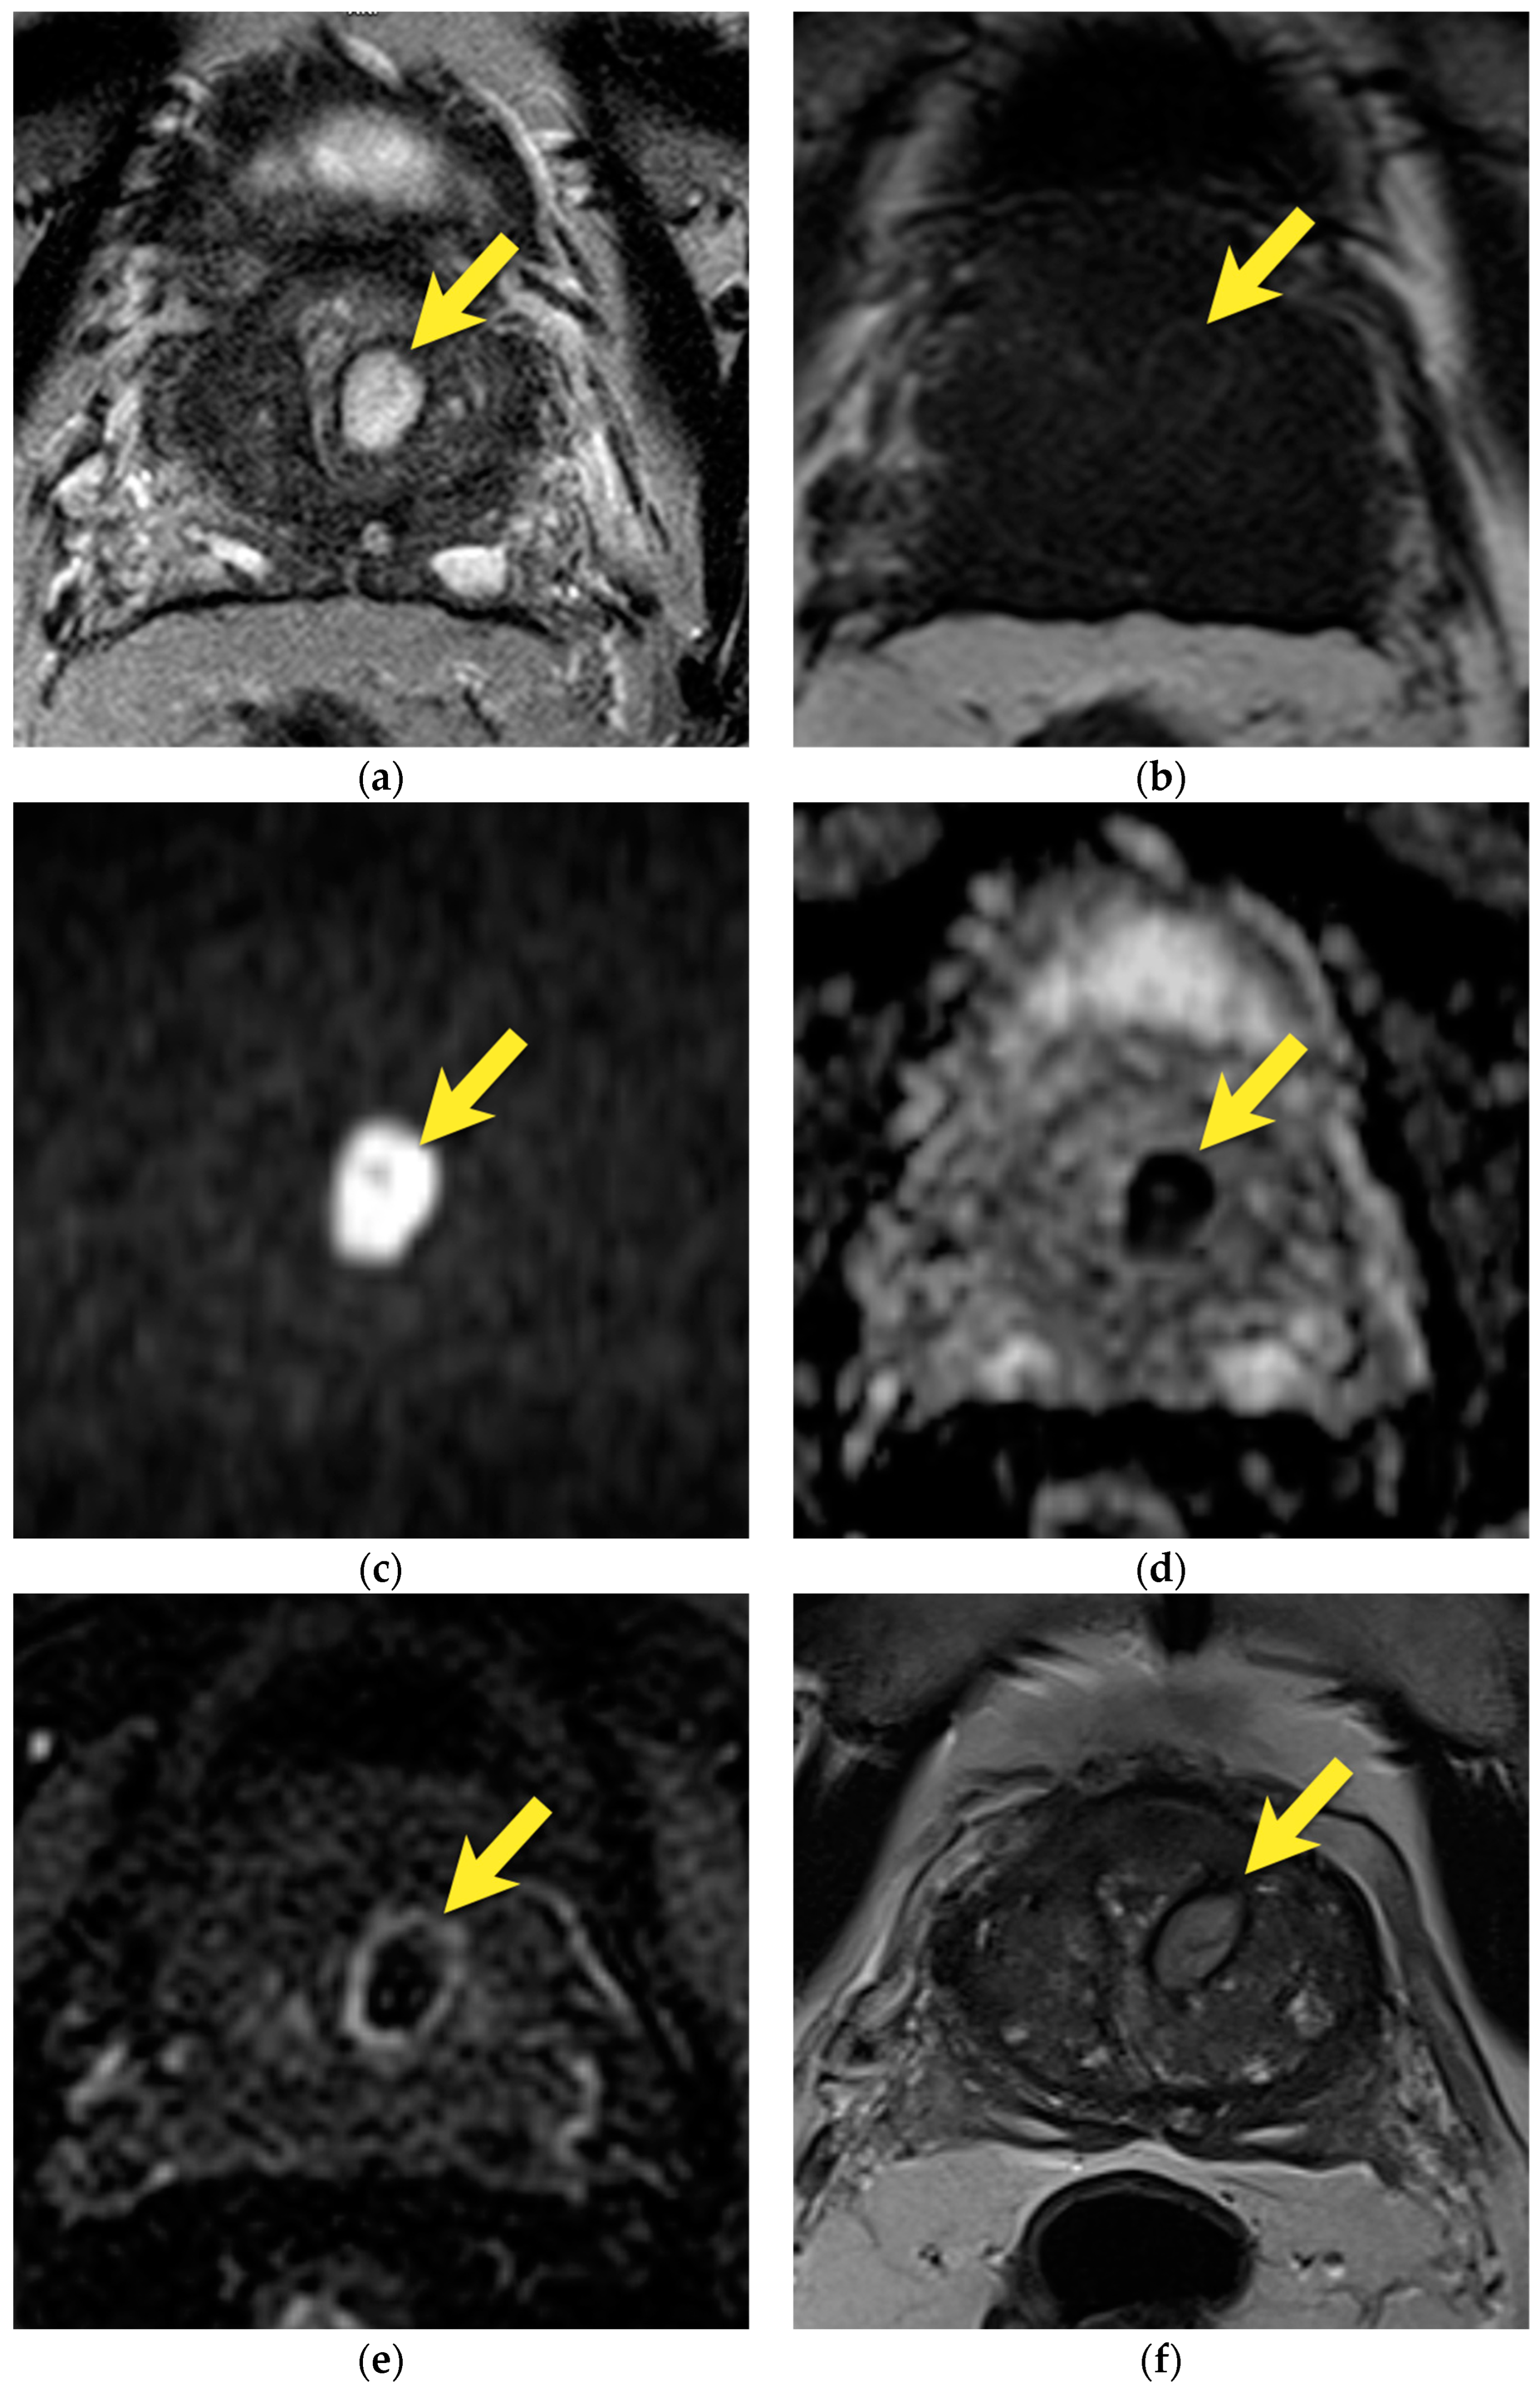

11. Quality of Images

8. Post-Biopsy Hemorrhage